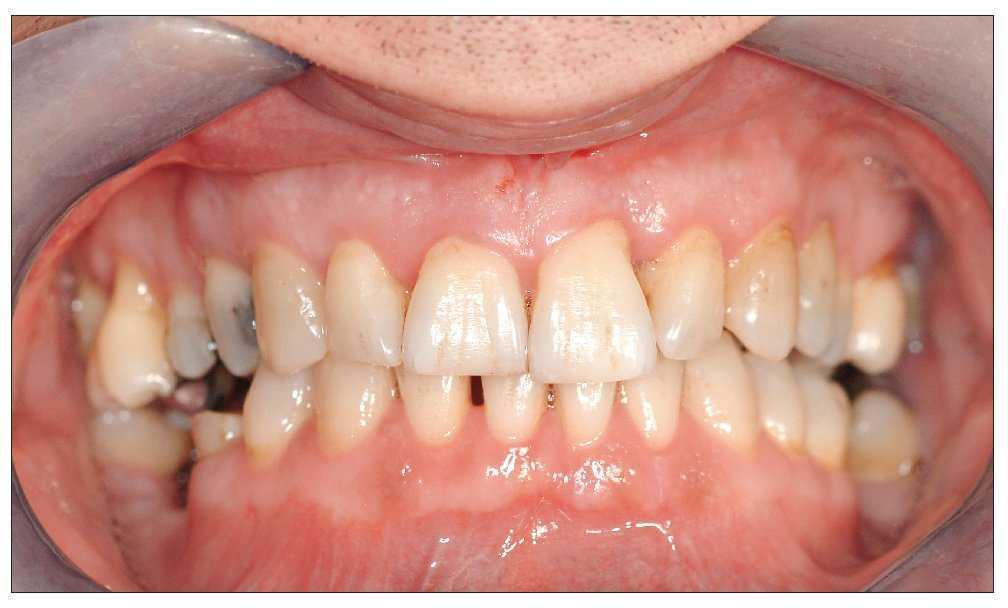

Uno o dos años después de iniciar el tratamiento, el cuadro es clínicamente y radiológicamente estable con una ganancia de inserción clara y profundidades de sondaje fisiológicas incluso en los dientes 31 y 21, cuyo pronóstico inicial era desfavorable (figs. 7 y 8a a 8c). El odontólogo que derivó al paciente puede asumir a partir de este momento el tratamiento restaurador posterior.

Figura 8. Situación clínica dos años después del inicio del tratamiento: se aprecia un periodonto estable sin alteraciones.